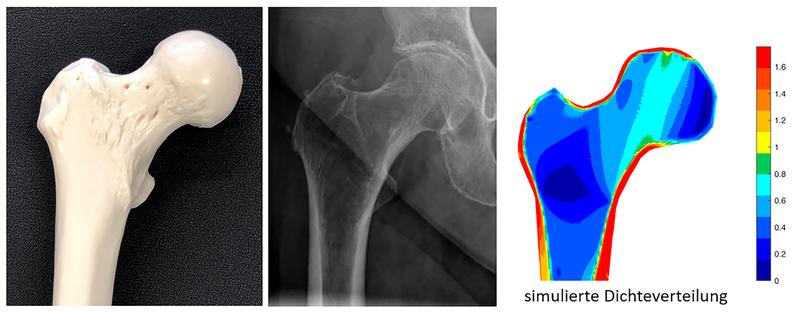

Prof. Dr.-Ing. Areti Papastavrou von der Fakultät Maschinenbau und Versorgungstechnik der TH Nürnberg leistet mit ihrem Forschungsprojekt „OSTEO-MODEL“ einen wichtigen Beitrag dazu. Ihr Ziel ist es, wesentliche Prozesse des Knochenumbaus zu simulieren und daraus mögliche Therapieansätze abzuleiten. Mit Hilfe der Finite-Elemente-Methode (FEM) modellieren sie und ihr Forschungsteam das Wachstum und die Degeneration von Knochen. Die Finite-Elemente-Methode ermöglicht eine rechnerische Simulation und wird normalerweise bei Bauwerken oder anderen Konstruktionen eingesetzt, um deren Verhalten, beispielsweise bei starkem Wind, vorauszubestimmen. Das Forschungsteam um Prof. Dr.-Ing. Areti Papastavrou setzt die Methode ein, um die Veränderungen der Knochenstruktur zu bestimmen. „Bei unseren Simulationen können wir unterschiedliche Randbedingungen mitberücksichtigen, wie die mechanische Beanspruchung des Knochens durch Bewegung und Belastung. Auch Aspekte der Ernährung, die den Stoffwechsel des Knochens über Vitamine oder Hormone beeinflussen, können wir in unsere Berechnungen einfließen lassen“, so Prof. Dr.-Ing. Areti Papastavrou.

Ausgangspunkt für die Simulationen sind anonymisierte Bilddaten von Knochen betroffener Patientinnen und Patienten, die mittels Computertomografie (CT) aufgenommen wurden. Diese lassen Rückschlüsse auf die Knochenmasse und Schädigungen wie Mikrorisse zu. Mit diesen Daten berechnet das Forschungsteam die Festigkeit des Knochens im FE-Modell. Zudem kann das Team eine Einschätzung abgeben, an welcher Stelle der Knochen am wahrscheinlichsten unter einer bestimmten Belastung, wie Springen oder Fallen, brechen wird.

Für das Simulationsmodell greift die Forschungsgruppe auf bestehende Vorarbeiten zurück und erweitert diese um Aspekte des Knochenstoffwechsels und Hormonhaushalts. Außerdem können sie Modelle für weiche biologische Gewebe auf die Knochen anpassen und übertragen. Das so entstandene, neue Simulationsmodell haben die Wissenschaftlerinnen und Wissenschaftler mit etablierten Verfahren und mit realen klinischen Befunden verglichen – es liefert dabei sehr gute Ergebnisse.